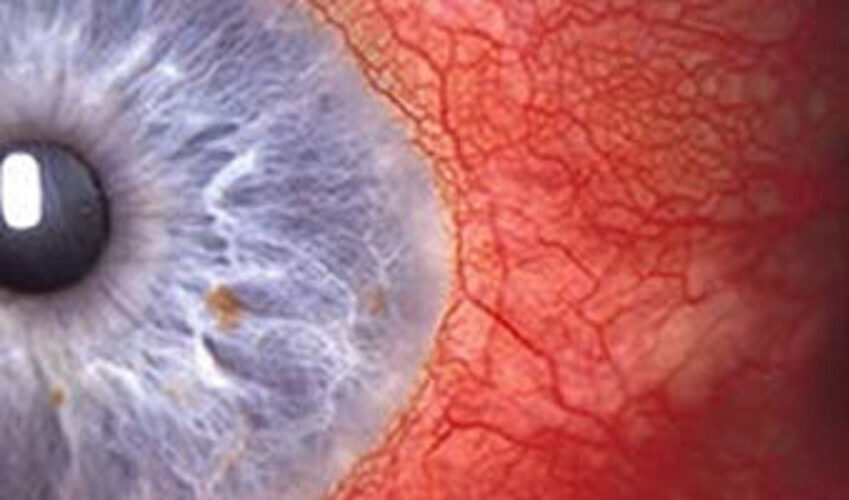

Das Rote Auge

Es handelt sich hierbei um eine Erweiterung der Blutgefässe, um Blutungen aus undichten Blutgefässen oder eine vermehrte Blutfülle in der Bindehaut aufgrund eines Entzündungsreizes (Reiz aus der Lederhaut, der Hornhaut, der Regenbogenhaut oder den Lidern). Abhängig von der Ursache kann es schmerzhaft sein oder nicht, mit oder ohne Entzündung einhergehen.

Die wahrscheinlichste Ursache für ein rotes Auge ist eine Bindehautentzündung (Konjunktivitis). Ein rotes Auge kann jedoch auch ein Zeichen einer ernsteren Augenerkrankung sein, die bei einer Verzögerung der Behandlung aufgrund einer fehlenden/falschen Diagnose zu einem dauerhaften Sehverlust führen kann. Diese Augenerkrankungen sind akutes Winkelblockglaukom (plötzlicher Augendruckanstieg, Iritis (Entzündung der Regebogenhaut), Keratitis (Hornhautinfektion) und Skleritis (Entzündung der Lederhaut). Merkmale wie starke Schmerzen, Photophobie (Blendung), verminderte Sehschärfe und eine einseitige Präsentation sind "rote Ampeln”, dass ein sehbedrohlicher Zustand vorliegen könnte.